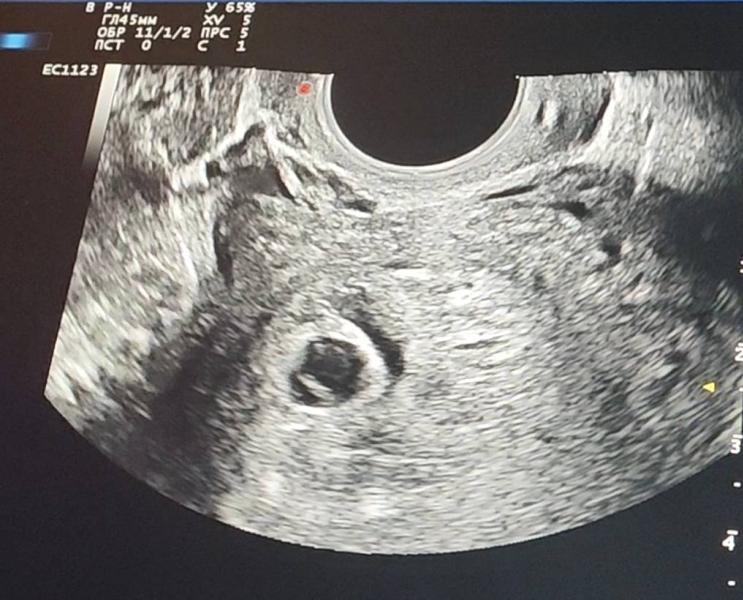

А вчера прям каплю мазануло 🩸и я решила утром поехать на УЗИ. Почему кровило- не понятно. Шейка закрыта, варикоза нет.

Крошка совсем крошечная. Овуляция точно поздняя была, но всё равно так понимаю, что отстаёт. Сердцебиение 85 ударов, тоже слабовато. По календарю срок 7,4, по моим подсчётам - 7,1.

А это не гематома на узи? Если это она , может она кровила ?

@puziriki темное пятнышко рядом с пя очень похожа на гематому , я не врач , но у меня были (